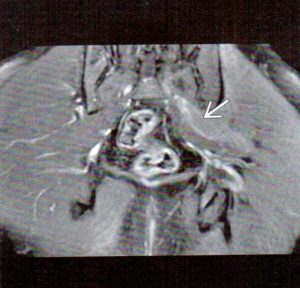

I have included 3 images from 3 different patients to illustrate some typical MRI findings in piriformis syndrome. Figure 1 is a fat-suppressed coronal image. The arrow points to the left piriformis muscle, which exhibits an increased signal intensity when compared to its right-sided counterpart.